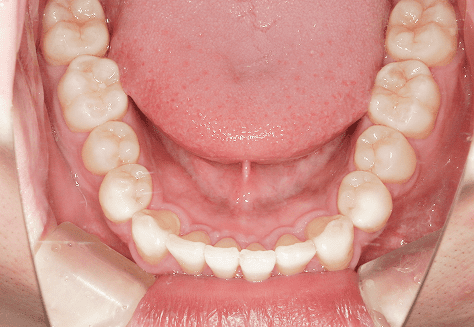

M.U

治療前

治療後

主訴

下の歯が特にガタガタなのが気になる。上の前歯が1本反対になっている。

診断

下顎前突・叢生・反対咬合

年齢/性別

20代/男性

抜歯部位

非抜歯

使用装置

上下インビザライン(PBM使用)

保定装置

ビベラリテーナー

料金

初回資料採得・・・・・・・30,000円

診断料・・・・・・・・・・33,000円

動的治療終了時資料採得・・5,500円 -

基本料金

950,000円

診察料金

5,500円×16回

-

治療期間

1年7カ月